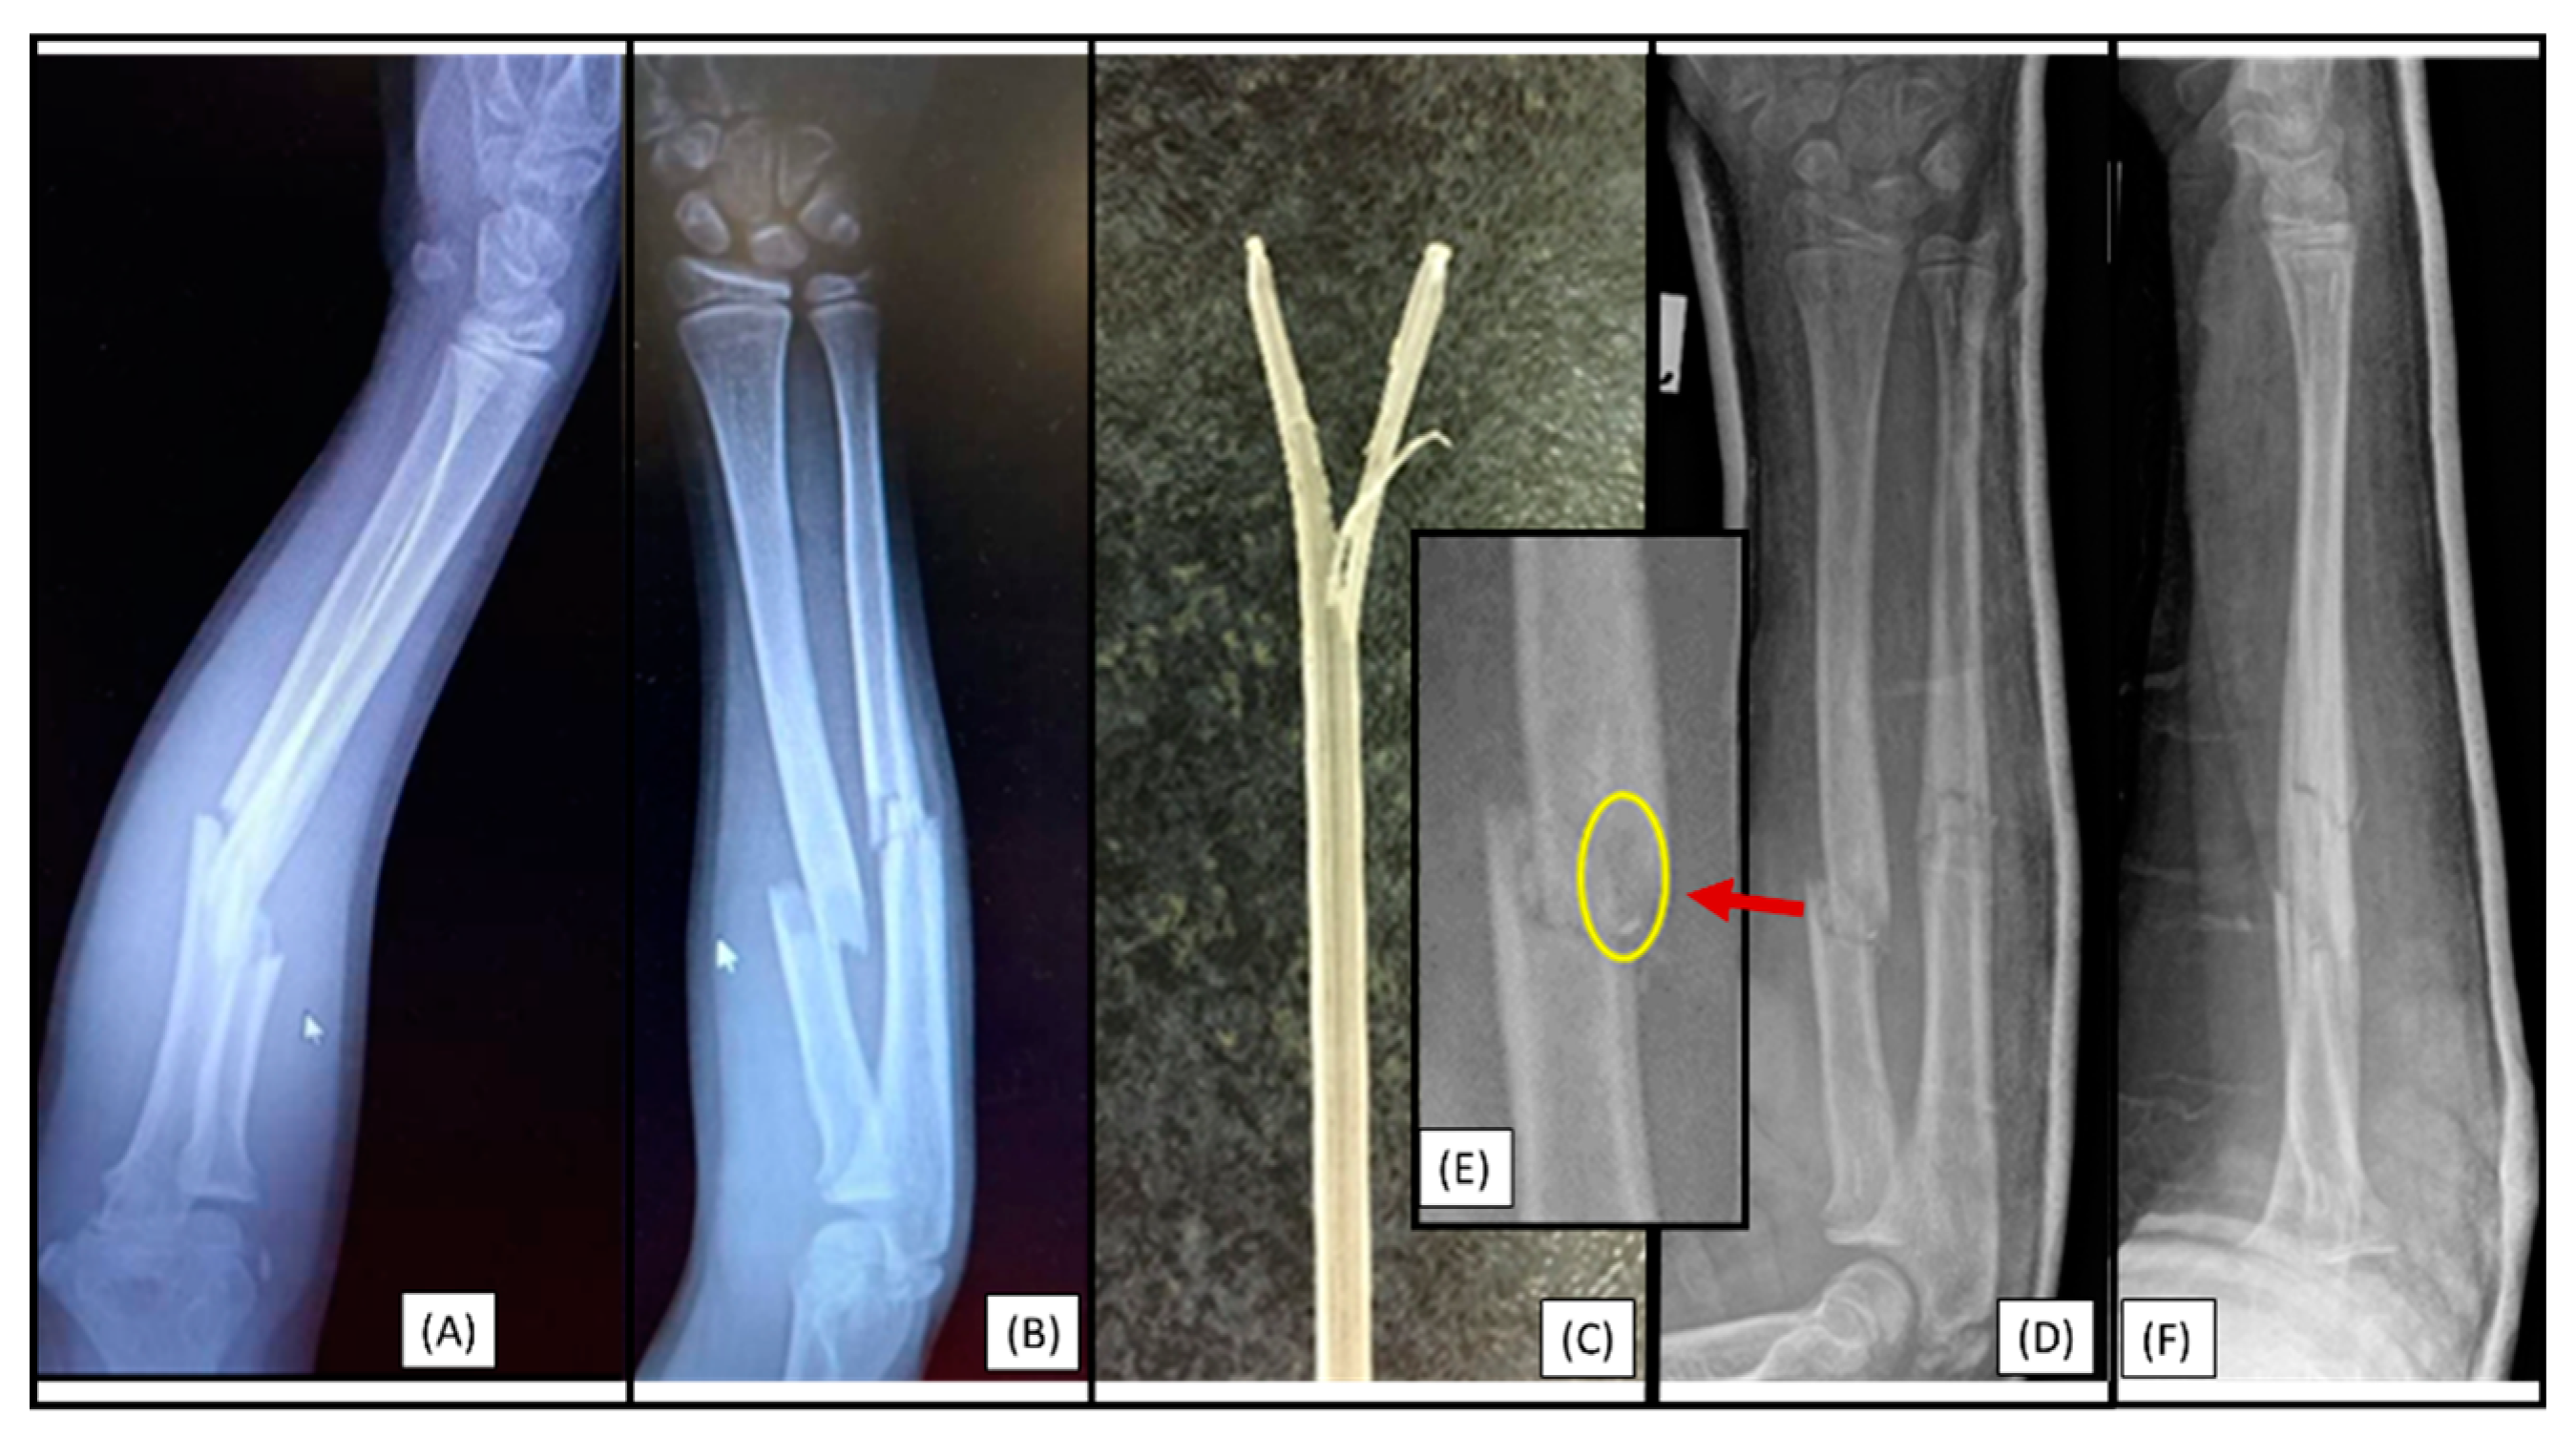

A 12-year-old boy's left forearm was injured during a handball match. X-rays confirmed a distal dia-metaphyseal forearm fracture. Following the closed reduction of a left distal diaphyseal forearm fracture, due to instability, the (2.7 mm) dilator was introduced through a typical radial approach, which resulted in cortical perforation on the opposite side (Figure 1(C)). Preparation of the medullary cavity is crucial when using absorbable IM implants. Although this patient case did not involve an implant-related complication, it directly relates to the challenges associated with the surgical procedure. Therefore, when such intraoperative complications are observed, the use of absorbable implants is not recommended.

A 10-year-old child was injured while playing on a trampoline. He suffered a complete (22-D/4.1.) fracture of the right forearm. Following the closed reduction of a complete proximal third forearm fracture and proper preparation of the medullary cavity, the introduction of the (3.2 mm) absorbable IM PLGA implant at the fracture site was difficult (Figure 3(A-B)). The BIN could not be passed through the fracture gap, and the β-TCP marking was visible outside the bone's medullary cavity, projecting onto the interosseous membrane. After removal of the implant, we observed that the end of the nail had split (Figure 3(C)). This can be explained by challenges in surgical technique that led to an implant-related complication (implant failure) and due to the fact that after losing the precise reduction, the introduction of the absorbable implant was forced, causing it to break. Therefore gentle implant insertion in case of obstruction is preferred, like withdrawing and repeating the preparation of the medullary cavity with an appropriately sized dilator.

Figure 1. Primary X-rays of a distal diaphyseal forearm fracture from anteroposterior (AP) and lateral views (B). After the insertion of the dilator (blue line), the opposite cortical was perforated (red line). Following this intraoperative complication, elastic nails were inserted, and both bones were stabilized with ESINs. Postoperative X-ray demonstrates good alignment (C).

Figure 3. Initial X-rays of the diaphyseal forearm fracture (lateral (A), AP (B)) and the split end of the resorbable IM nail (C). Postoperative images (lateral (D), AP (F)) show good alignment of the bones, but the magnified AP view (E) demonstrates a two mm displacement of the radius, which caused the injury of the implant. .